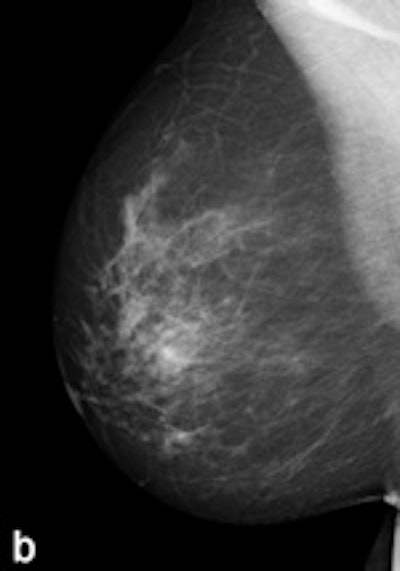

| Example of a subtle finding in a right-sided mediolateral oblique view, which was only reported by radiologists when using premium view (PV). A: Digitized prior. B: Tissue equalization (TE) processed image. C: PV processed image with the annotation. D: The resulting image of subtracting TE from PV. E: Thresholded version of D. White areas indicate that pixels in the PV image have relatively higher intensity than the related pixels in the TE image, whereas black areas indicate the opposite. In PV images, low-frequency trends are suppressed (no noticeable signal decrease in the breast edge in PV compared with TE), whereas higher-frequency structures are emphasized (e.g., glandular structures). All images courtesy of Wouter Veldkamp, PhD, Leiden University Medical Center. |

The cases were acquired using the Senographe Essential digital mammography system (GE Healthcare). Tissue equalization is a standard GE application that corrects for low-frequency variations resulting from under- and overpenetration of x-rays. As a result, the image dynamic range is reduced, enabling improved soft-copy image display.

The local contrast optimization, premium view, has been designed to improve the quality of the information presented to the radiologist for diagnosis and also the reading speed by optimizing the local contrast in breast structures. In premium view, low-frequency structures are obtained from the original image by low-pass filtering. High-frequency structures are obtained by subtracting the low-pass filtered image from the original image. The low- and high-frequency images are both processed and weighted individually, then added together. The resulting image exhibits reduced contrast between different tissue types but enhanced contrast of small-scale anatomical architecture.

Another example of a finding in a left-sided craniocaudal view that was reported clearly more often by radiologists when using premium view (PV). A: Tissue equalization (TE) processed image. B: PV processed image with the annotation. C: Similar to image above, the resulting image of subtracting TE from PV. D: The thresholded version of C.For all six radiologists, perceived case suspiciousness -- defined as the highest probability of malignancy of all radiologist findings -- was higher using premium view optimization.